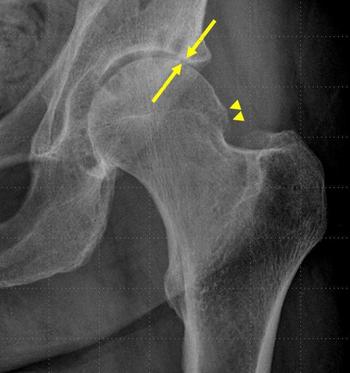

X-rays show that patients with osteoarthritis who receive a hip steroid/anesthetic injection may develop osteonecrosis of the hip.